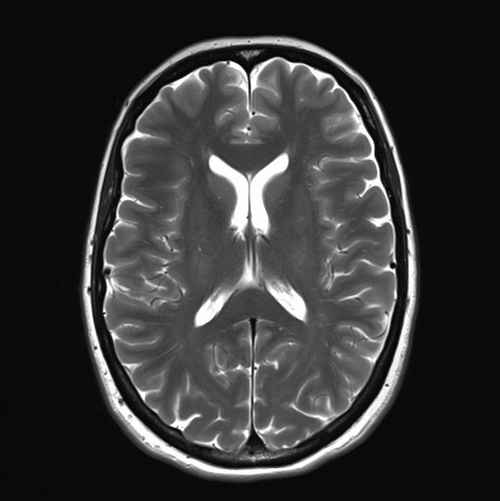

We have a huge number of cases with different modalities and regions

By Modality